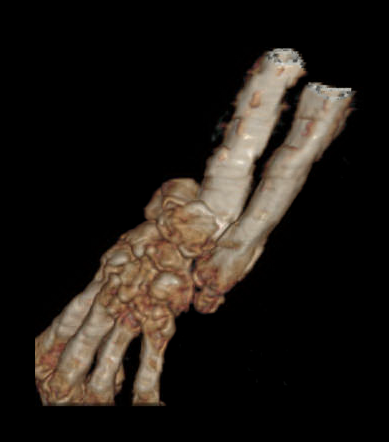

术前腕关节CT

2、左桡骨远端骨折